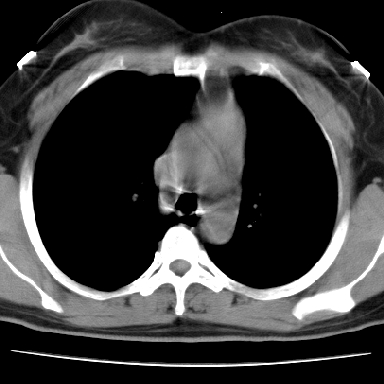

左下肺有空洞,壁厚薄不均,壁结节,两肺多发小结节影,腋窝下可疑淋巴结肿大,综上所述考虑周围性肺癌并两肺转移可能性大,建议穿刺活检。

右肺多发小结节影,边界清楚,符合转移瘤的特点;2、左下肺偏心性空洞影,右侧乳腺内高密度影,需要查体除外右侧乳腺肿瘤;3、腋窝淋巴结肿大,考虑转移。

支持癌性空洞:壁厚,无液平,内壁不规则,外壁呈分叶状,较大,偏心性,壁结节,胸膜凹陷,转移灶。